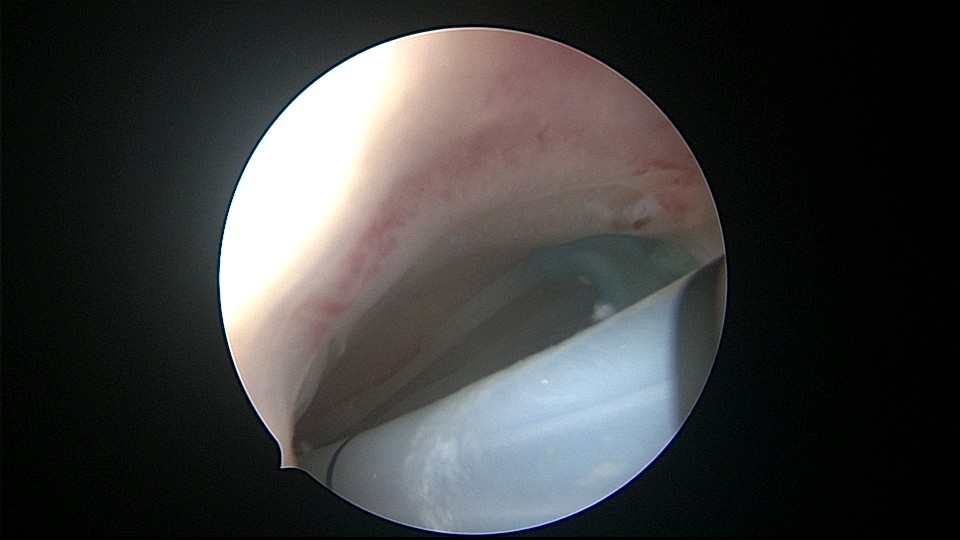

患者29岁,G1P0,继发不孕,2020年8月宫腹腔镜探查,大网膜与腹前壁多处粘连,子宫后壁与直肠前壁广泛粘连,宫腔中央型宽大柱状粘连,宫腔两侧少许粘连。电钩分离盆腔粘连,冷刀分离宫腔粘连,恢复宫腔形态,显露双侧输卵管开口,术中美兰通夜,双侧输卵管通畅。2020年10月宫腔镜二探取球囊,宫腔形态正常,双侧输卵管开口可见。2021年3月自然妊娠,外院足月分娩。现34岁,G2P1。